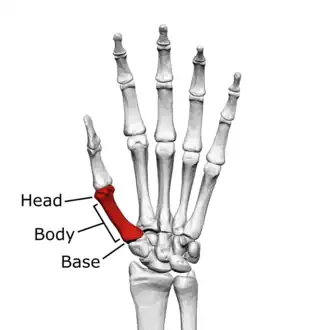

The first metacarpal bone or the metacarpal bone of the thumb is the first bone proximal to the thumb. It is connected to the trapezium of the carpus at the first carpometacarpal joint and to the proximal thumb phalanx at the first metacarpophalangeal joint.

The first metacarpal bone is short and thick with a shaft thicker and broader than those of the other metacarpal bones. Its narrow shaft connects its widened base and rounded head; the former consisting of a thick cortical bone surrounding the open medullary canal; the latter two consisting of cancellous bone surrounded by a thin cortical shell. [1]

Head

The head is less rounded and less spherical than those of the other metacarpals, making it better suited for a hinge-like articulation.

The distal articular surface is quadrilateral, wide, and flat; thicker and broader transversely and extends much further palmarly than dorsally. On the palmar aspect of the articular surface there is a pair of eminences or tubercles which articulate with the radial and ulnar sesamoid bones of the thumb metacarpophalangeal joint; the lateral eminence is larger than the medial.

Body/Shaft

The body or shaft is thick and broad — averaging 6 to 11 millimetres (0.24 to 0.43 in). On its dorsal side, the shaft is flat and wide, while the anteroposterior side is less pronounced; usually resulting in an oval-triangular cross-section.

The dorsal surface of the shaft is weakly convex longitudinally, while its palmar, radial, and ulnar surfaces tend to be concave. The palmar and medial surface exhibits a blunt ridge which separates a larger lateral part – the insertion of the opponens pollicis muscle – and a smaller medial part – the origin of the lateral head of the first dorsal interosseous muscle.

Base

The base is significantly different from the bases of the other metacarpals. It is trumpet-shaped and ends in a saddle-shaped articular surface matching that of the trapezial articular surface. The configuration of the thumb carpometacarpal joint plays an important role in the mechanism of opposition. The articular surface is delimited by a thick, crest-like ridge extending around its circumference.

On the palmar and lateral side of the base is the insertion of the tendon of the abductor pollicis longus muscle, usually featuring a small tubercle. The origin of the first dorsal interosseous muscle is on the ulnar aspect of the base, and can sometimes extend onto the shaft. In contrast to the other metacarpals, the first metacarpal has no articular facets on the sides of its base (for intermetacarpal articulations) because it articulates exclusively with the trapezium.